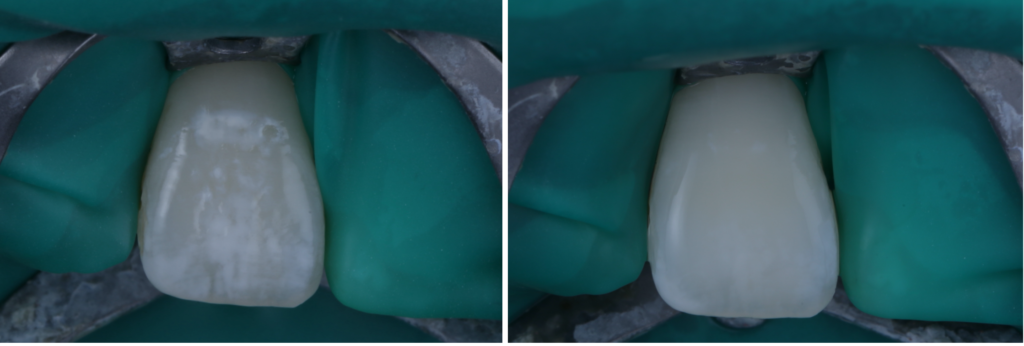

「歯の表面にある**茶色い点(ブラウンスポット)と、前歯に広がる白く濁った模様(ホワイトスポット・白濁)**が気になって…」

歯の白濁が気になる方へ|削らずに改善を目指す「ICON(アイコン)治療」

最近、「歯の白濁が気になる」「前歯の白い斑点が目立って笑いづらい」と感じていませんか?鏡を見たときや写真に写った自分の歯を見て、違和感を覚えたことがある方は意外と多いものです。歯の白濁は痛みがないことがほとんどですが、見た…